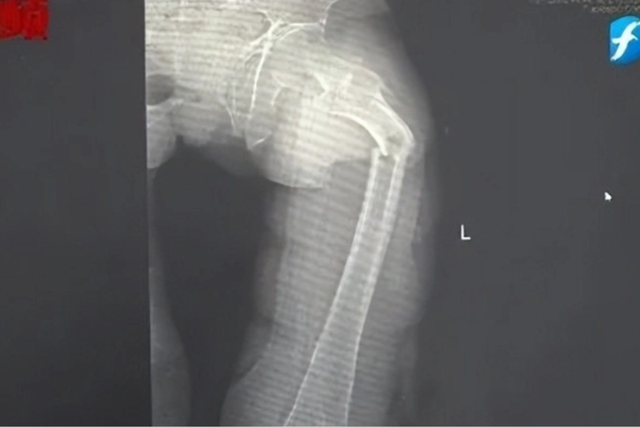

Một người đàn ông họ Cung (Phúc Kiến, Trung Quốc) bị gãy xương đùi nghiêm trọng sau một cơn ho dù mới 35 tuổi. Theo anh Cung kể lại, gần đây mình bị cảm lạnh nhưng không muốn uống thuốc nên cứ ho và sổ mũi dai dẳng không khỏi. Buổi tối hôm đó, anh ăn đồ hơi lạnh nên càng ho dữ dội. Trong một lần ho, anh đột nhiên cảm thấy đau nhói ở đùi trái. Anh cho rằng mình bị chuột rút nên không quá quan tâm, cố gắng nén đau và đi ngủ.

Đến nửa đêm, anh Cung bị giật mình tỉnh giấc vì cơn đau ở đùi. Anh phát hiện ra mình không thể đi lại được nhưng cố chờ đến trời sáng hẳn rồi nhờ người nhà đưa đi bệnh viện. Kết quả chụp X-quang tại Bệnh viện Nhân dân số 2 Phúc Kiến (Trung Quốc) khiến anh Cung sốc nặng: xương đùi trái của anh bị gãy làm hai mảnh chỉ vì một cái ho.

Bác sĩ Đông Trung, Trưởng khoa Chấn thương và Chỉnh hình của bệnh viện cho biết anh Cung bị gãy xương bệnh lý, xảy ra do loãng xương sớm rất nghiêm trọng. Dù mới 35 tuổi nhưng xương của anh Cung được bác sĩ nói vui là “xốp như tổ ong”, khối lượng xương tương đương với một cụ già 80 tuổi.

Theo bác sĩ Đông Trung: “Ở độ tuổi trưởng thành, gãy xương đùi thường chỉ xảy ra sau những tác động mạnh như tai nạn giao thông hay rơi từ độ cao lớn. Tuy nhiên, trong trường hợp của bệnh nhân, anh bị loãng xương sớm.